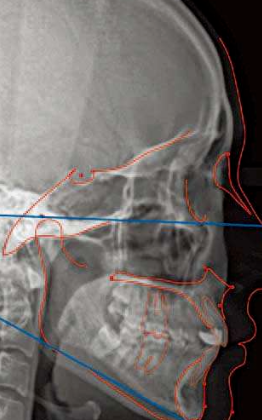

上、下颌骨形态及位置关系判断